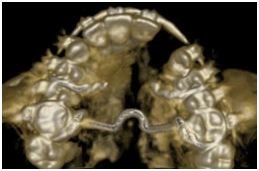

• Observar pacientes portadores de fenda palatina

Vista axial Reconstruções 3D